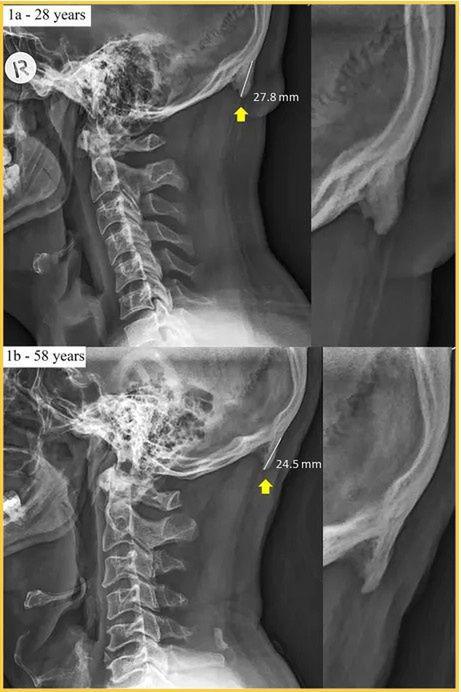

Naukowcy wskazują, że w grupie osób pomiędzy 18 a 30 lat u 40 proc. badanych wykryto specyficzną narośl kostną zlokalizowaną w tylnej części czaszki, która nie występuje u większości ludzkiej populacji.

Według badań nowy wyrostek kostny może mieć długość ok. 3 cm, a powodem jego pojawienia się jest nagminne nachylenie kręgosłupa szyjnego związane z korzystaniem ze smartfonów.

Badacze twierdzą, że organizm wykształca nową narośl aby zrównoważyć „wirtualny” ciężar, który może sięgać nawet 27 kilogramów.